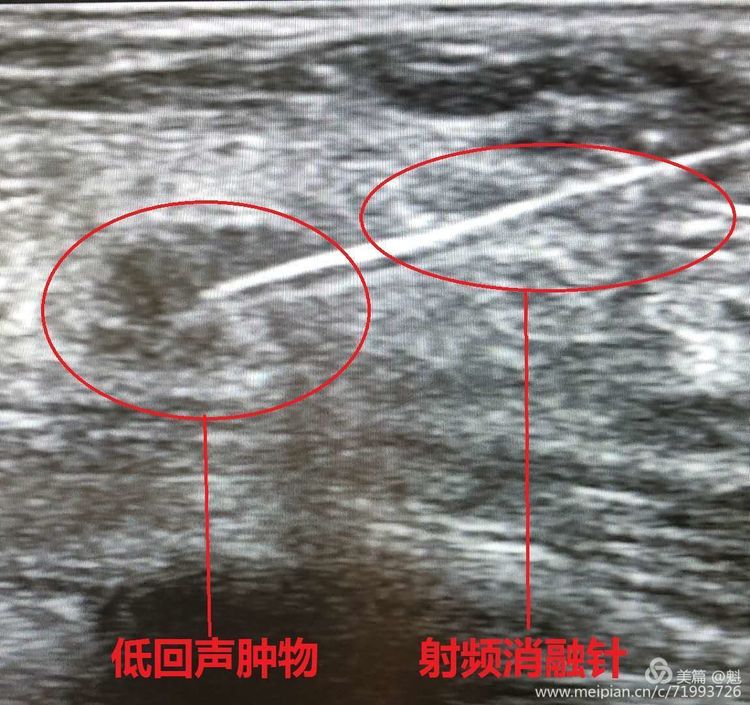

漯河市中心医院普外二科病房设在一号病房楼16楼,实际开放70张。普外二科是漯河市卫生局的普外科重点专科,上海交通大学附属九院血管外科医联体单位,华中胃肠腔镜联盟理事单位、河南省人民医院胃肠外科联盟成员,中原糖尿病足联盟成员、郑大一附院甲状腺外二科医联体成员,郑州大学第一附属医院河南省肝胆胰疑难疾病诊治联盟单位,中国医师协会结直肠肿瘤专委会NOSES专委会会员单位。2004年即获得漯河市“肝胆血管外科”重点专科。2013年获得首批省卫计委审核周围血管介入及综合介入准入资质,能独立开展血管及综合介入四类手术。2015年获漯河市“肿瘤微创血管外科”重点专科。2017年省青年文明号先进...